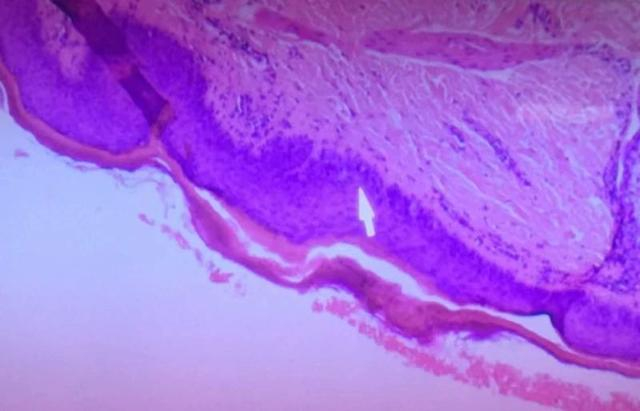

近日她来到上海市皮肤病医院就诊,做了皮肤的活检,病理科主任刘业强看诊后发现问题的罪魁祸首就是李女士经常使用的消毒液。这是一种含有苯扎溴铵的消毒液,长期使用此消毒液浸泡或者清洁衣服,诱发其导致一种叫“颗粒状角化不全”的皮肤疾病。

“颗粒状角化不全”皮肤病的确切病因和诱因目前仍不明确,相对多见于外用除臭剂或止汗剂、消毒剂的人,病理表现为角化不全伴角质层透明角质颗粒残留。李女士所用的消毒液含有苯扎溴铵。这是一种表面活性剂,因为有灭菌作用,而且刺激性低,经常会用于消毒剂和洗涤剂中。既往文献表明,其有效成分浓度为70g/L或以上的苯扎溴铵容易导致疾病。据介绍,针对“颗粒状角化不全”的治疗需要停用消毒液,辅以糖皮质激素或保湿剂的外用,疗效不一。